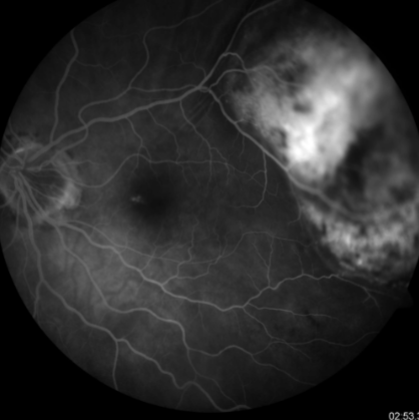

mottled fluorescence in arteriovenous phase, progressive staining, prolonged dye retention, double circulation

what does a choroidal melanoma show on IVFA?

choroidal melanoma

melanoma

melanoma

melanoma

melanoma

melanoma

melanoma

melanoma

melanoma

melanoma

melanoma

melanoma

melanoma

melanoma

melanoma

melanoma

melanoma